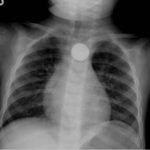

Button Battery in Esophagus

Chest radiograph showed the presence of a round radiopaque foreign body in the mid-chest. It was suspected to be in the esophagus rather than in the trachea due to the en-face positioning of the foreign body. The foreign body demonstrated two concentric ring circles concerning for a “double ring” or “halo” sign, which was suggestive of the presence of a button battery rather than a coin.

This patient underwent esophagoscopy with subsequent removal of a 2 centimeter lithium button battery; direct visualization showed some edema around the mucosa but no signs of stricture or perforation. The patient subsequently tolerated food and was discharged home the next day.